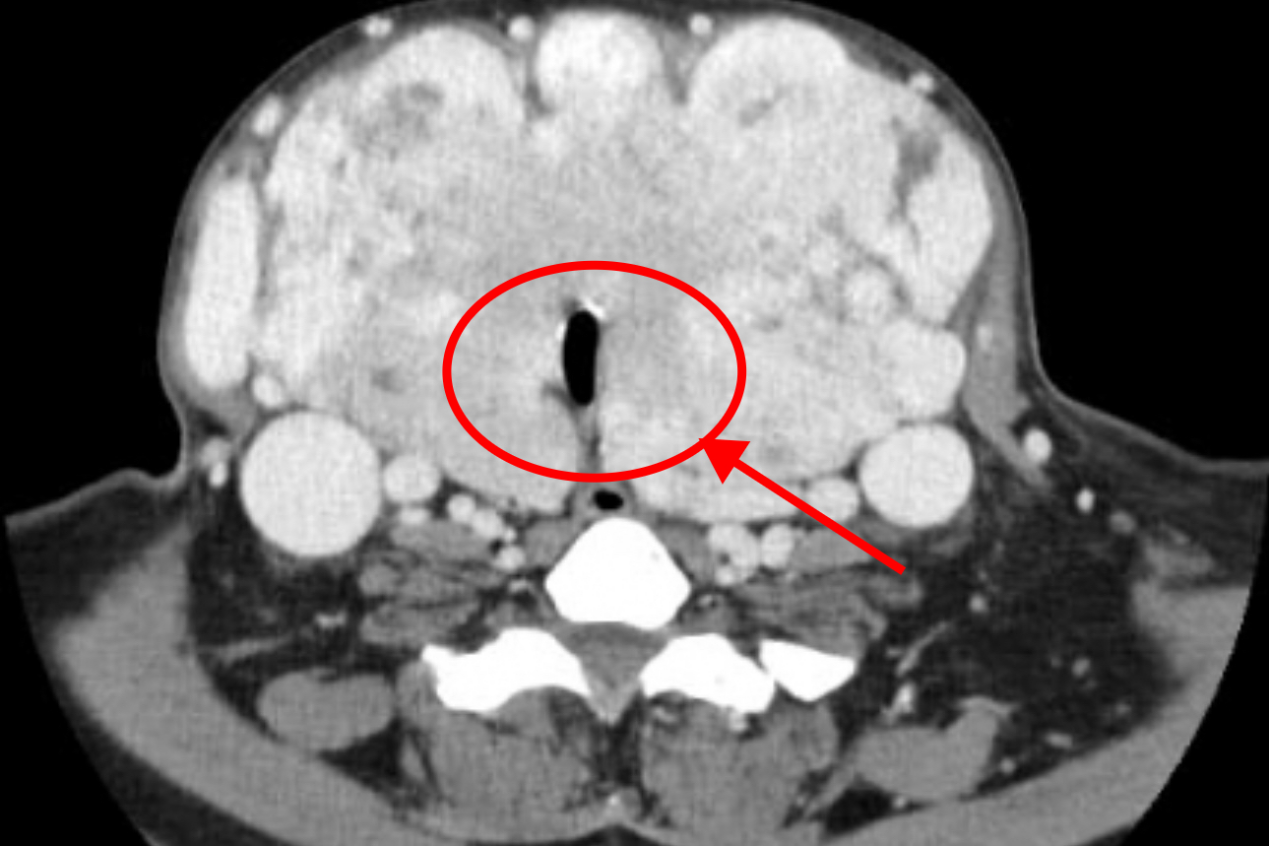

近期,贵黔国际医院成功完成一例极高风险的巨大甲状腺肿切除手术。据乳腺甲状腺科杨新华主任介绍,患者王女士(化名)年仅39岁,11年前被确诊甲亢,经初期抗甲亢治疗有效,后因不规范治疗,长期服用抗甲亢药物引起甲减,导致甲状腺代偿性增大,最终甲减越来越严重,甲状腺也越来越大。肿大的甲状腺不仅让患者无法低头,而且已经把气管压得只剩一条狭窄的缝隙,影响到呼吸,患者无法平卧,再加上继发心衰,患者随时可能出现生命危险。

“手术是唯一的生路,但难度很大,风险很高。”杨主任表示,因为甲状腺太大,其血管也显著增多增粗,有些血管扩张至手指一样粗,血流非常丰富,侧支循环非常多,无法进行术前栓塞,喉返神经有可能被推挤至非正常位置,术中术后极易发生致命性大出血、双侧喉返神经损伤、气管塌陷坏死、窒息等严重并发症。加之王女士肿大的甲状腺严重影响日常生活,导致其无工作和经济来源,还需照顾长期卧床的父亲,无力承担手术费用,术后也无人照料。这重重的困难,让她的求医之路屡屡受阻。

8月6日,手术如期进行。术中发现甲状腺肿巨大且血供异常丰富,与周围组织粘连严重......手术团队精细操作,犹如拆除一枚身上的“炸弹”,最终凭借高超的技术和紧密的配合,成功将25厘米大小、重达935克、超过正常30多倍的巨大甲状腺肿完整切除,并完好保护了喉返神经以及甲状旁腺。